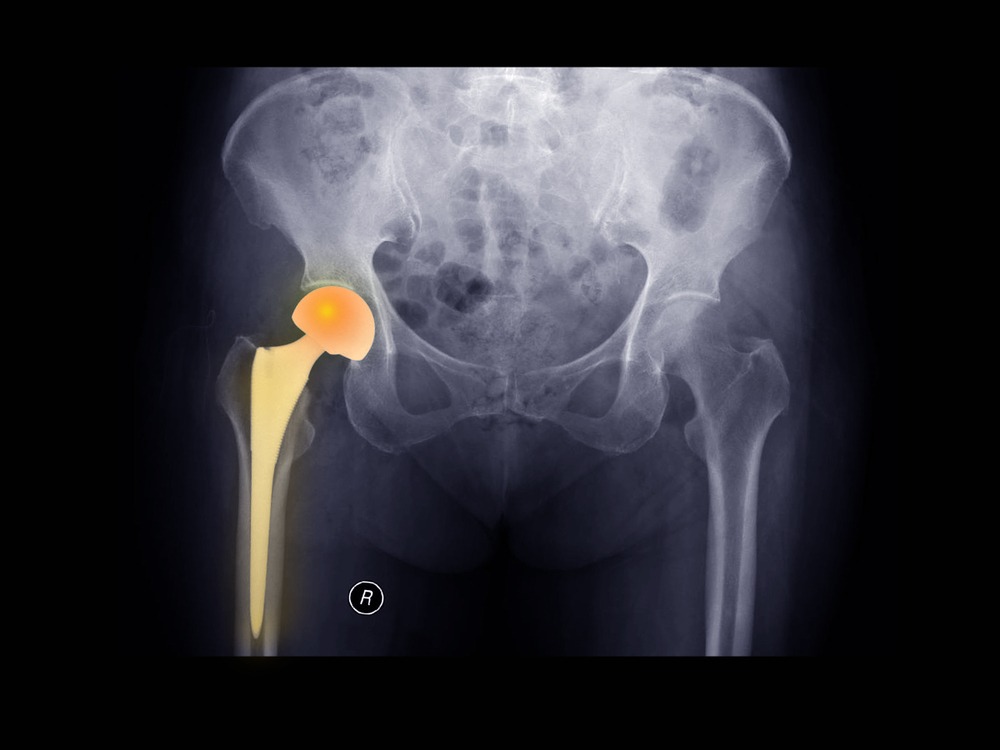

Κάταγμα Ισχίου. Πότε χρειάζεστε χειρουργική επέμβαση;

Περισσότερο σε ηλικιωμένους αλλά και σε άτομα νεαρής ηλικίας, το κάταγμα ισχίου αποτελεί έναν από τους συχνότερους τραυματισμούς. Επηρεάζει σημαντικά την κινητικότητα και συνολικά την …